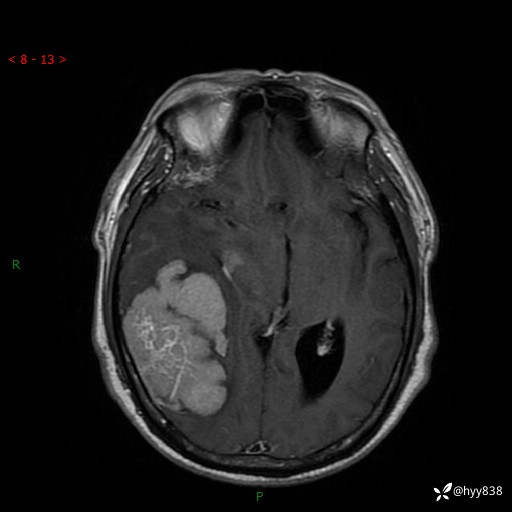

患者性别:男

患者年龄:56岁

简要病史:外院CT提示脑膜瘤,为进一步诊治来我院

辅助检查:MRI

临床诊断:颅脑占位

颅脑MRI平扫+增强